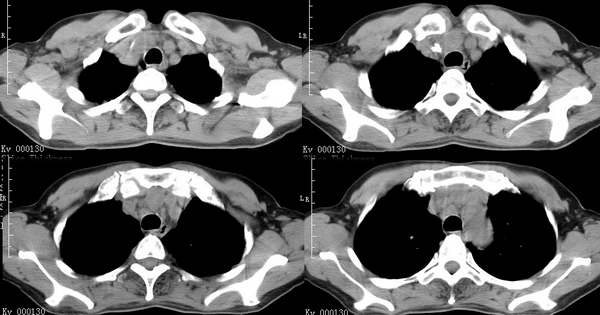

咳嗽6月低热1月!

右上叶背段及左下叶见斑片状密度不均模糊影,右中叶支气管狭窄,中叶密度增高,体积缩小.纵隔未见明确淋巴结.结论:1、两俩结核,右中叶支气管内膜结核,并中叶肺不张。2、两肺炎;右中心型肺癌,并阻塞性肺不张。

右肺上叶尖后段及左肺舌叶 下叶见斑片状密度不均模糊影,右中叶支气管狭窄,中叶密度增高,体积缩小.纵隔未见明确淋巴结。考虑:双肺结核伴右侧中叶不张。

右上叶背段及左下叶见斑片状密度不均模糊影,右中叶支气管狭窄,近端未见肿块,中叶密度增高,体积缩小.纵隔未见明确淋巴结.结论:两肺结核,右中叶支气管内膜结核,并中叶肺不张。肺纹理粗乱,有慢支表现,伴有感染存在。

ct显示病灶呈多灶性分布,主要分布在双肺上叶后段,右肺中叶及左肺下叶,右肺上病灶内可见点状钙化,纵隔内示淋巴结钙化,结合病史6个月伴低热,考虑感染性病变,结核可能大.